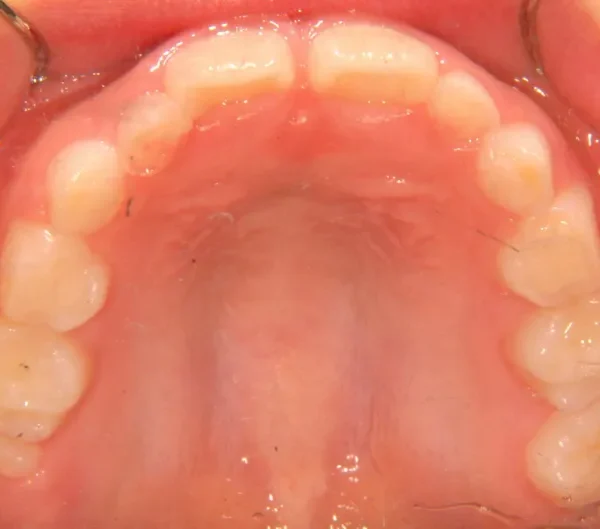

初診時年齢 小学校2年生 (男性) 主訴 癒合歯・永久歯が生えるスペースがない

診断名 叢生 装置名

上下の歯並びが狭く、永久歯の生える隙間がありません。

右下に癒合歯があり 上下の歯並びのアーチが悪くなっています。

オリジナルの着け外しのできる装置で治療しました。

治療回数○回、4年7ヶ月の治療期間で矯正治療を終了しました。

1期治療で十分な結果が得られたと思います。

治療終了後